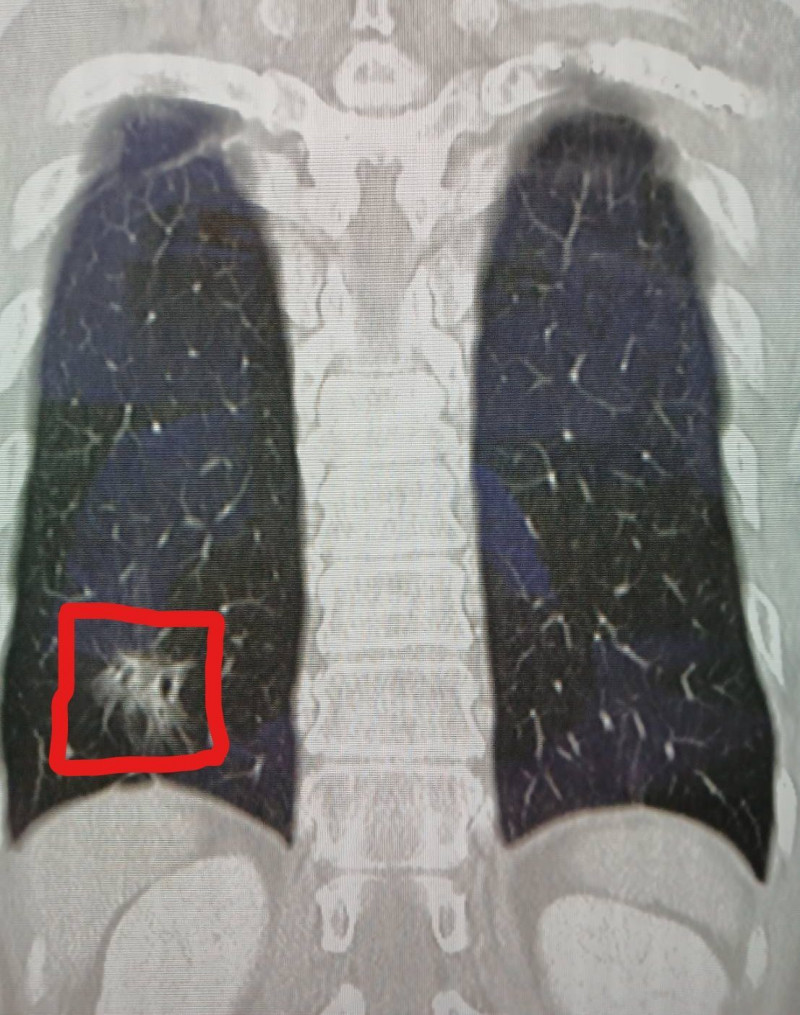

謝志明表示,醫療團隊在處理外傷的術前電腦斷層中,發現患者右下肺葉有疑似早期肺癌的毛玻璃樣病灶。待他肋骨傷勢穩定,3個月後回診追蹤時,檢查發現病灶依然存在。立即為他安排第2次「胸腔鏡微創手術」切除病灶,病理報告證實為肺腺癌第1期。